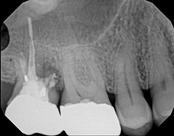

Apicoectomies, including molar apicoectomies:

Before

After

3-month follow-upThis person saw a specialist and was told the molar tooth needed to be extracted because the root canal failed and was infected. The root canal had been done by an endodontic specialist. The diagnosis was: previous endodontic treatment, chronic periradicular abscess. We did an apicoectomy and saved the patient’s tooth.